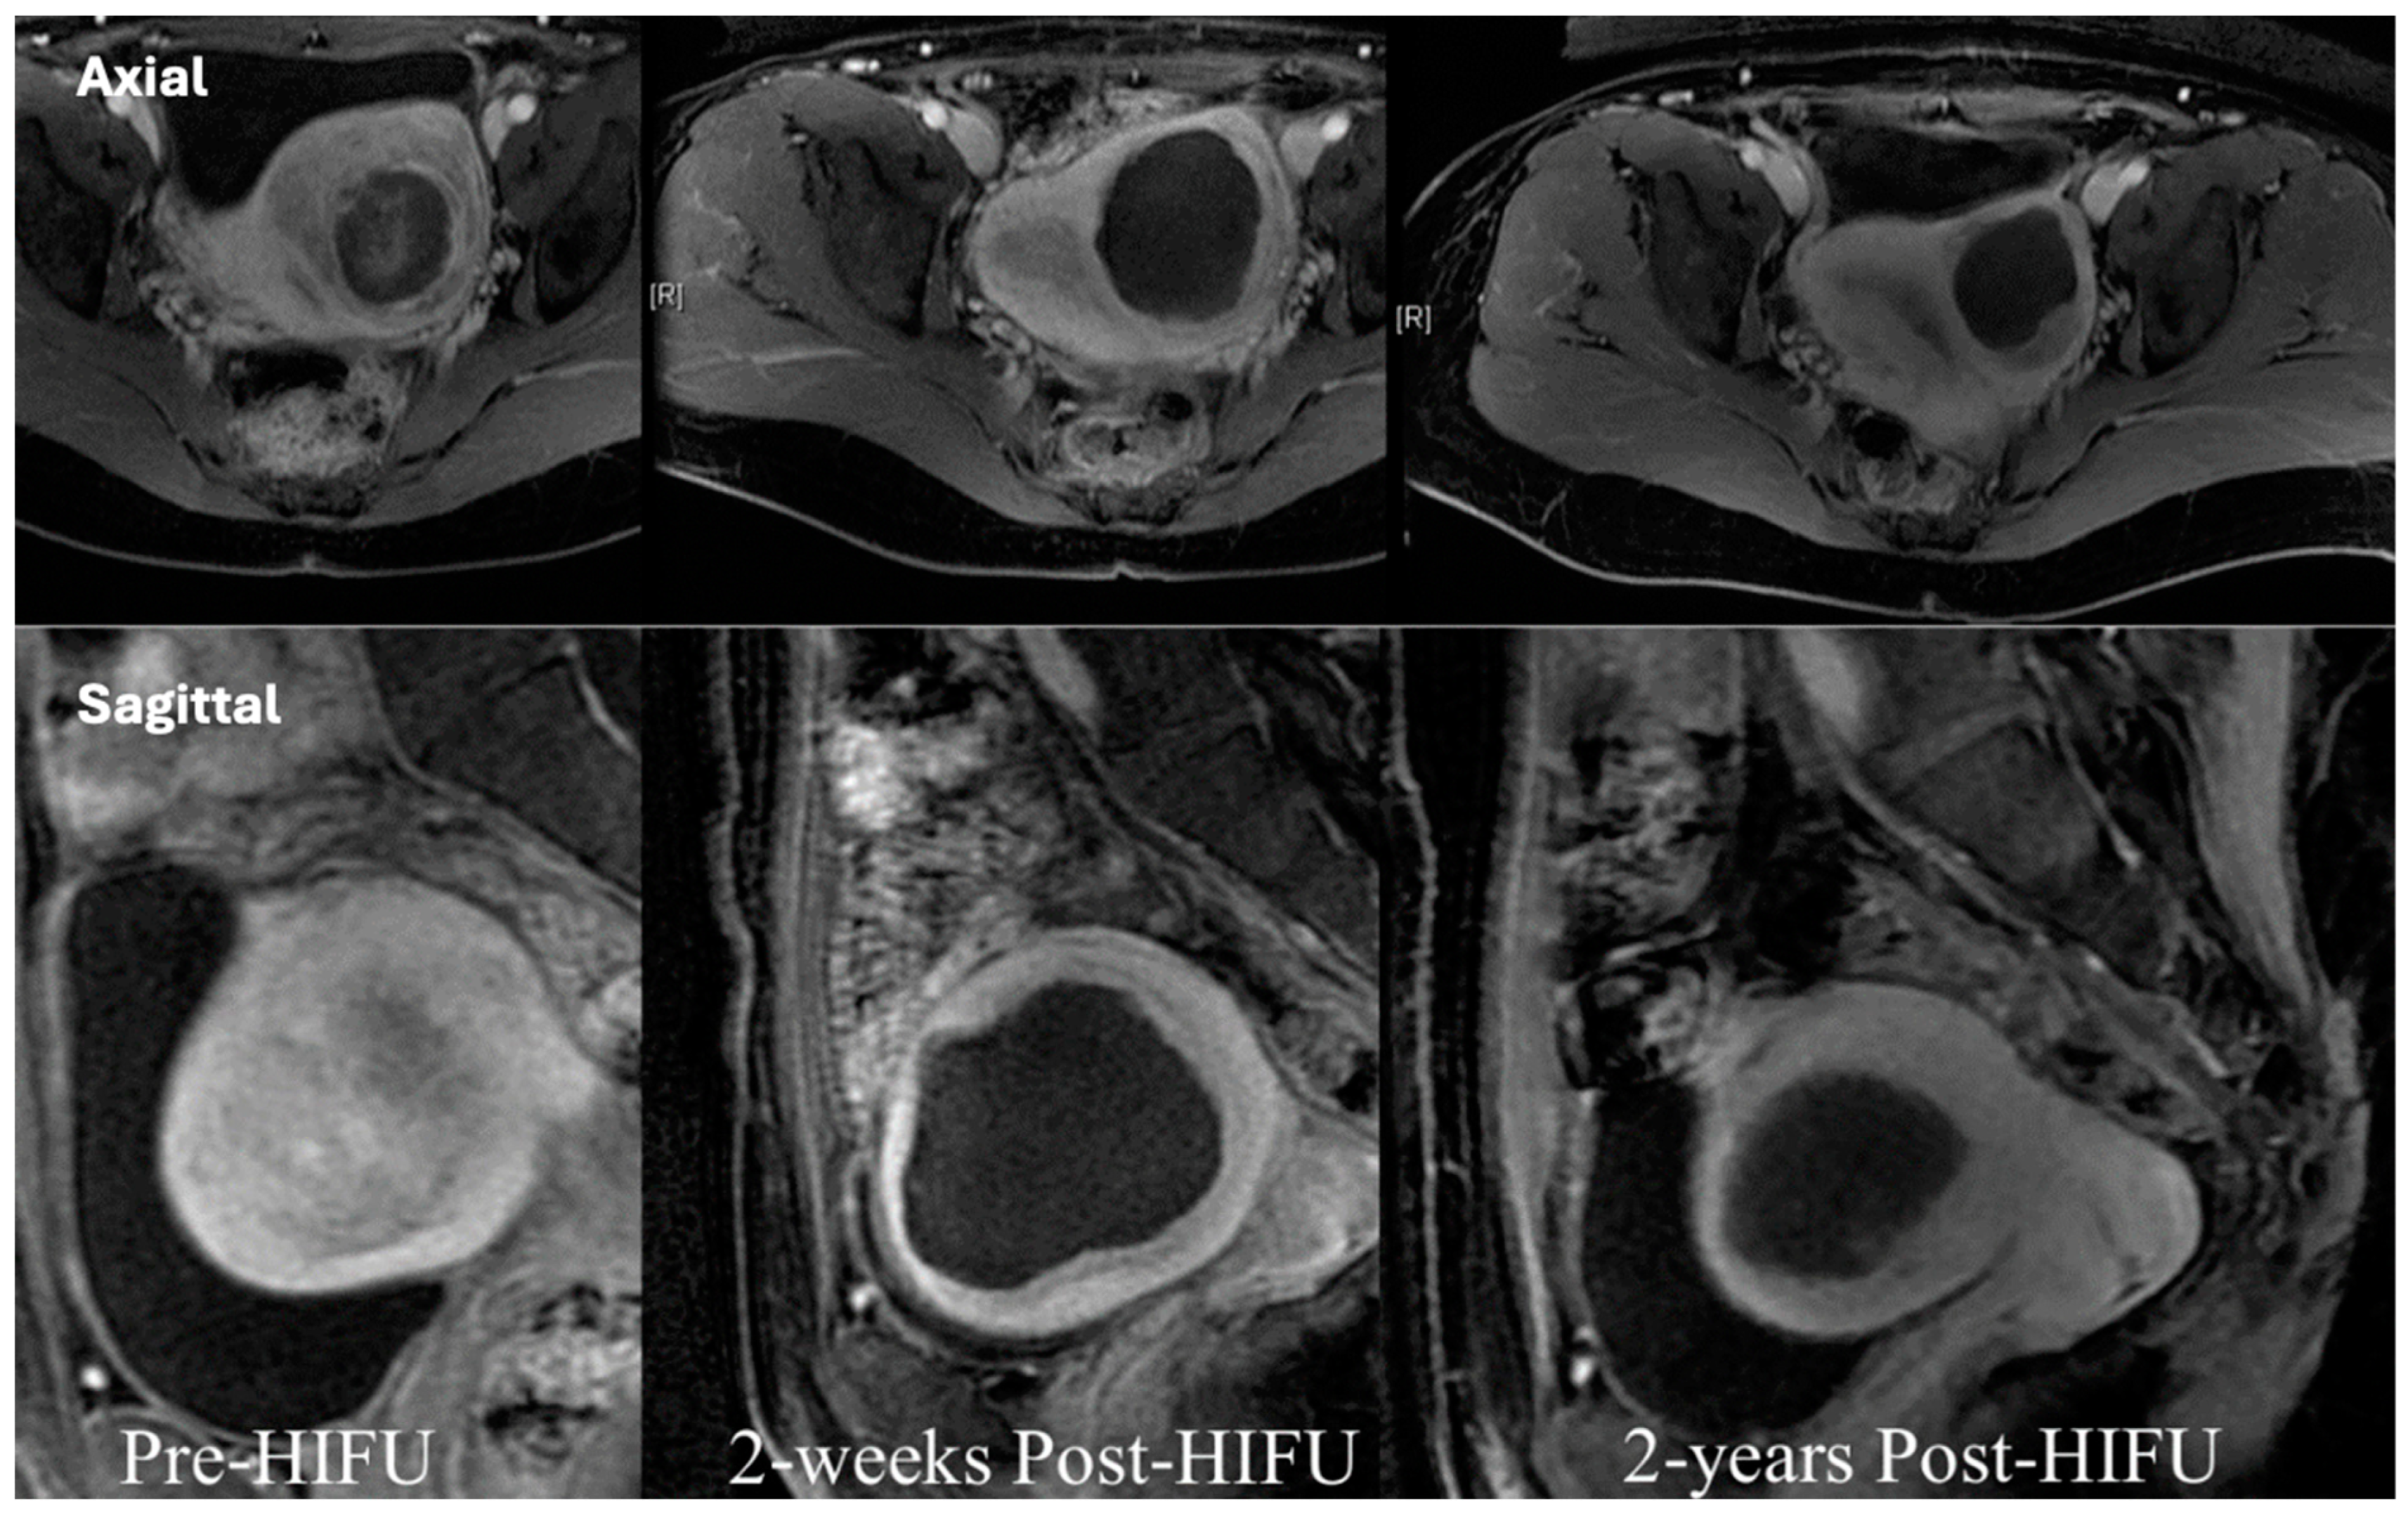

- Chetan, M.R.; Lyon, P.C.; Wu, F.; Phillips, R.; Cranston, D.; Gillies, M.J.; Bojanic, S. Role of diffusion-weighted imaging in monitoring treatment response following high-intensity focused ultrasound ablation of recurrent sacral chordoma. Radiol. Case Rep. 2019, 14, 1197–1201. [Google Scholar] [CrossRef] [PubMed]

- Gillies, M.J.; Lyon, P.C.; Wu, F.; Leslie, T.; Chung, D.Y.; Gleeson, F.; Cranston, D.; Bojanic, S. High-intensity focused ultrasonic ablation of sacral chordoma is feasible: A series of four cases and details of a national clinical trial. Br. J. Neurosurg. 2016, 31, 446–451. [Google Scholar] [CrossRef] [PubMed]

- Prachee, I.; Wu, F.; Cranston, D. Oxford’s clinical experience in the development of high intensity focused ultrasound therapy. Int. J. Hyperth. 2021, 38, 81–88. [Google Scholar] [CrossRef] [PubMed]